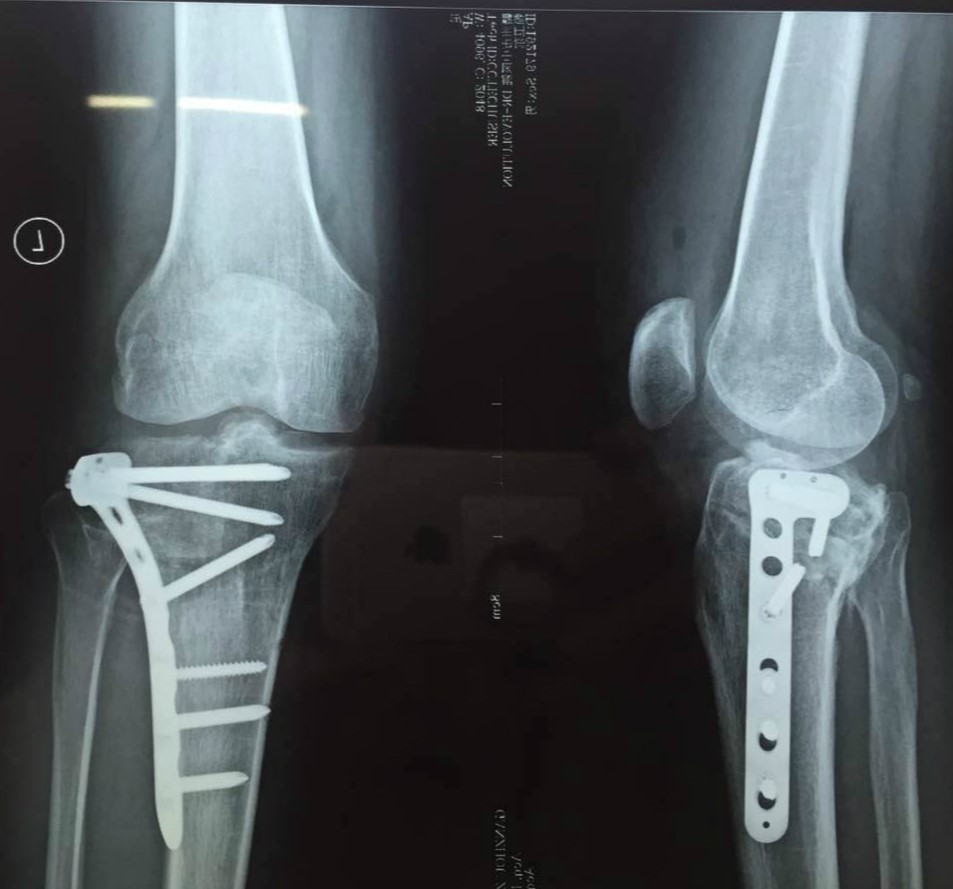

有了完美的術(shù)前規劃,那完美的術(shù)后效果也就不是奢望。

有了聞泰醫療數字骨科解決方案,運用3D打印技術(shù)幫助醫生進(jìn)行術(shù)前準備計劃,用軟件進(jìn)行手術(shù)入路模擬,3D打印骨折模型進(jìn)行手術(shù)復位模擬及內植物的選擇,以前的糾結不再。至于聞泰數字骨科更多功能揭秘,敬請關(guān)注我們的網(wǎng)站。